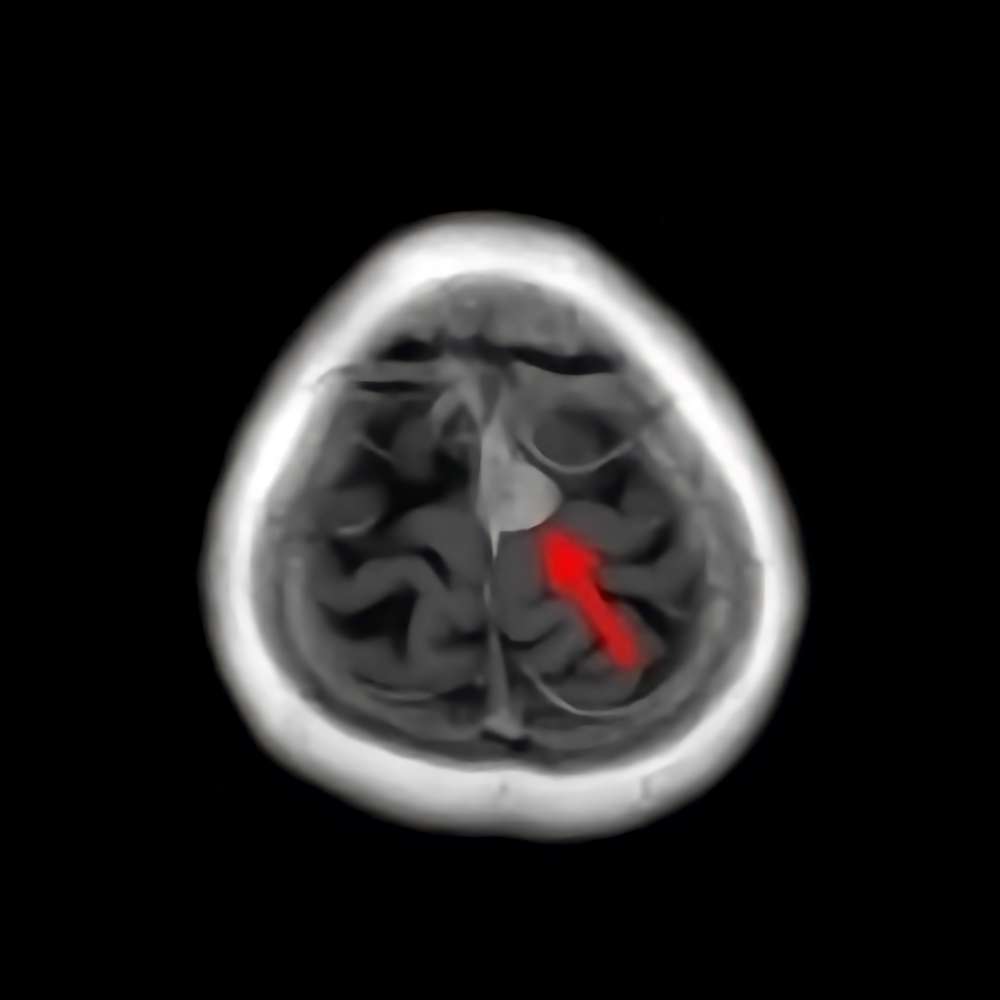

30代

海綿状血管腫

No.’15_49 手術前1

No.’15_49 摘出 前

No.’15_49 摘出 後